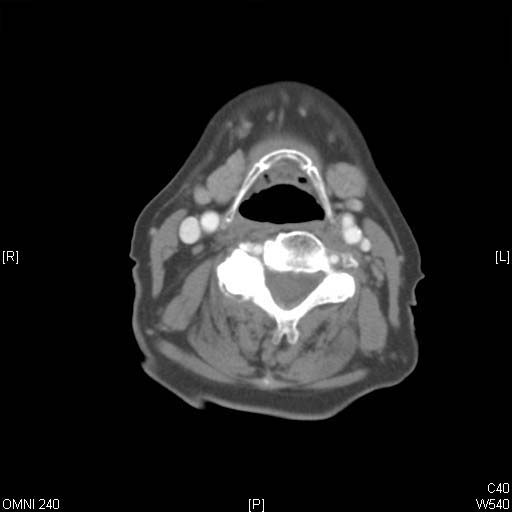

Identify Salivary gland and Hyoid